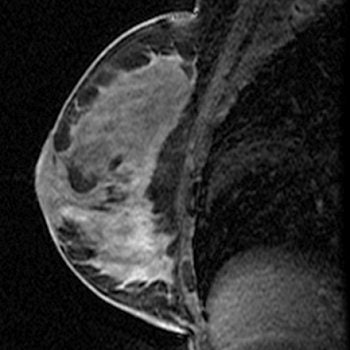

| A 63-year-old asymptomatic woman with family history of breast cancer who had abnormal right breast at MRI performed at outside facility. In sagittal T1-weighted contrast-enhanced image obtained after biopsy and clip placement at MRI-guided vacuum-assisted biopsy, lesion shows washout of contrast material, but no definite biopsy site changes are appreciated on this image. |